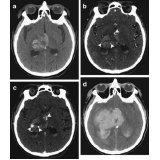

Às tomografias são uma maneira não invasiva e sem causar dor ao paciente, é usado um equipamento de raio x que ao passar ao redor do paciente cria várias imagens do interior do corpo, esse método é feito com rapidez e segurança. As imagens são analisadas e os dados possibilitam que seja feito um diagnóstico sobre o paciente, pois é permitido saber a forma, tamanho, densidade e textura do local dos órgãos do paciente, possibilitando fazer o diagnóstico e acompanhar tumores doenças infecciosas, traumas e distúrbios ósseos.